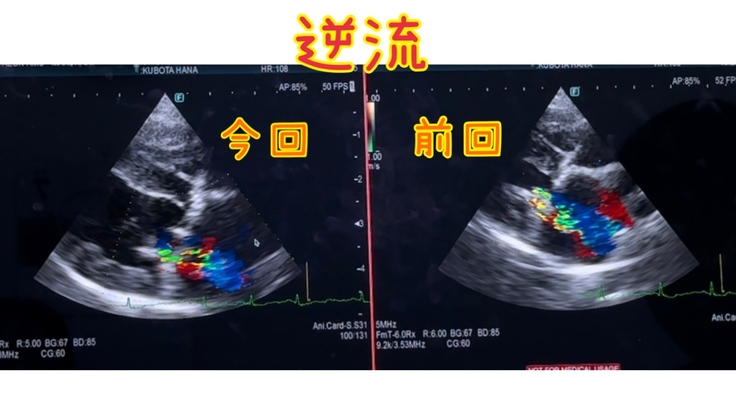

心臓手術後 11ヶ月検診でした

華の心臓手術後11ヶ月検診でした

心臓は、良くも悪くも変わりなしでした…

手術をした方の

逆流を無くせなかった箇所も

少しの逆流は、あるものの

変わりなし

右心の三尖弁の逆流は

中等度で変わりなし…